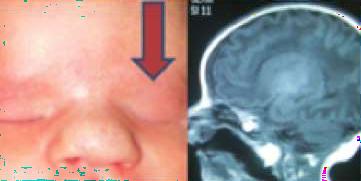

Introducción